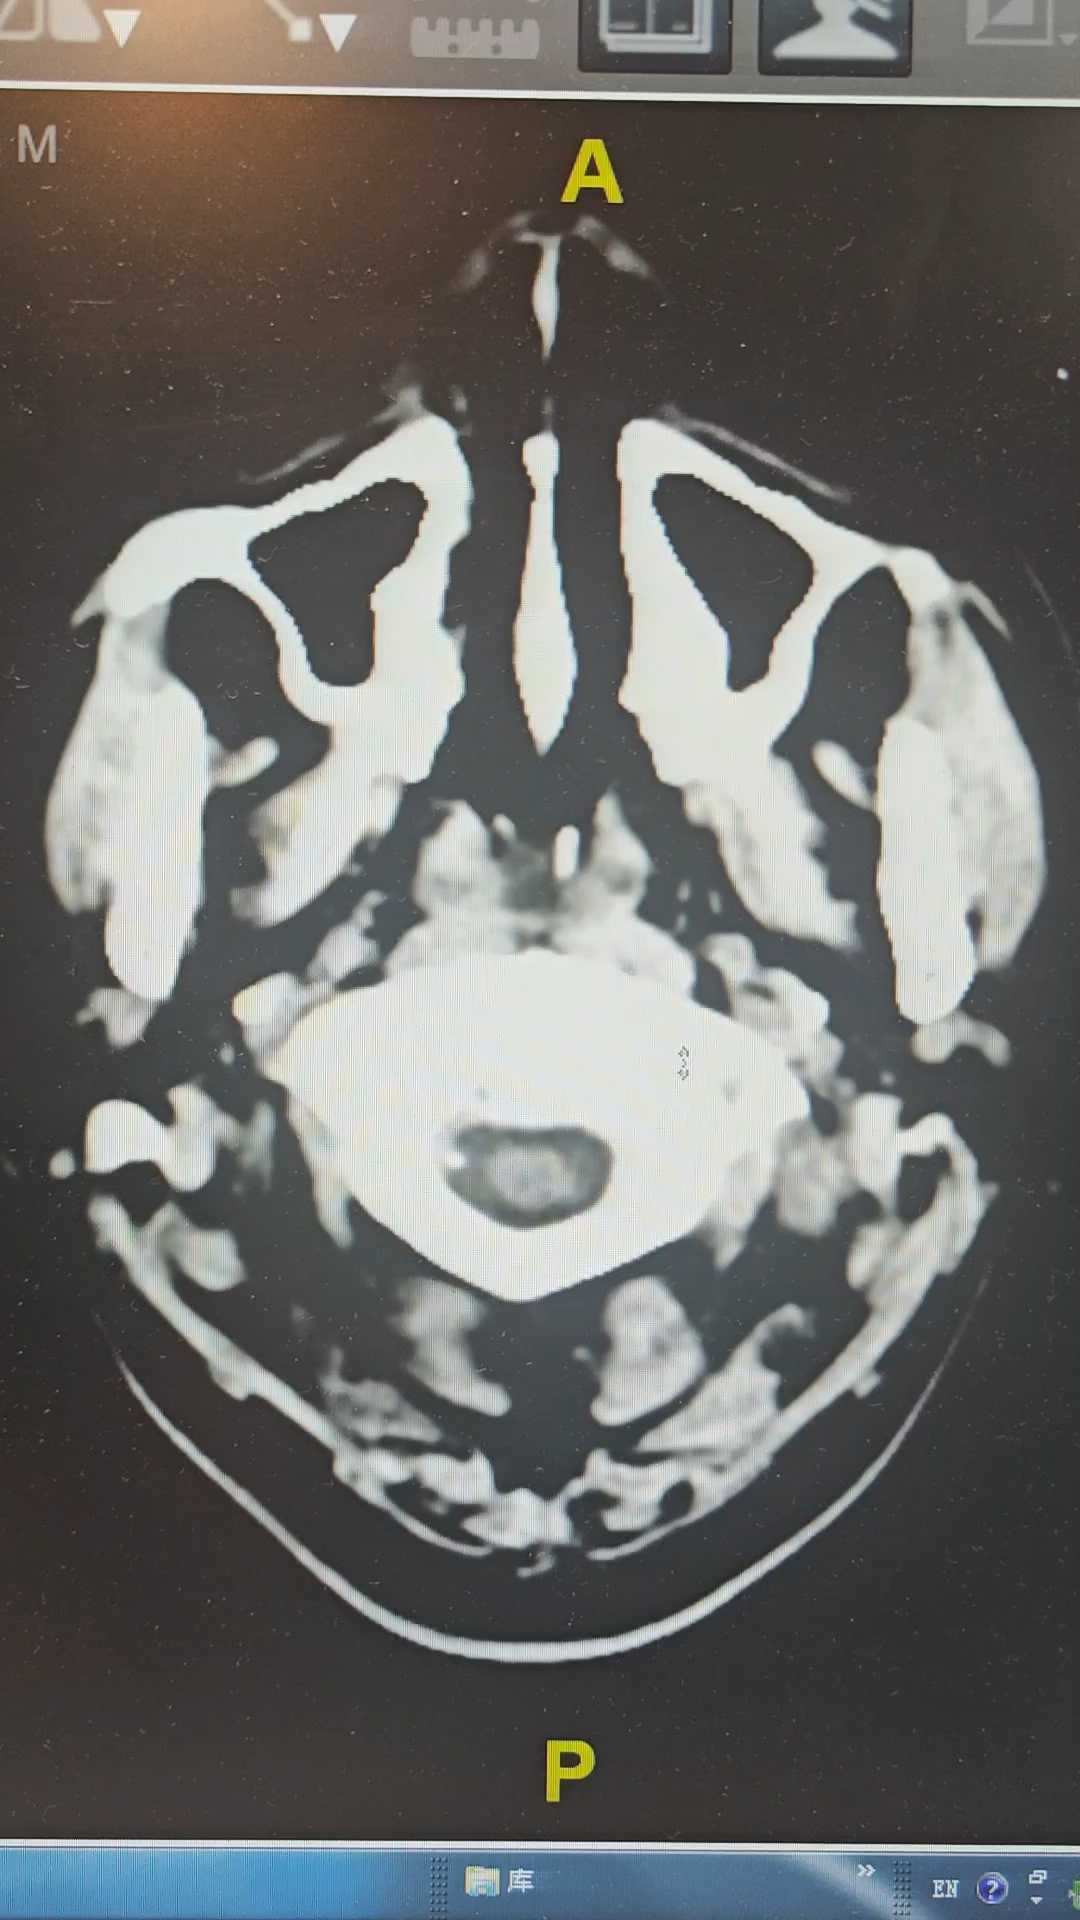

飞跃迷雾1 达人已点赞因“代:脑出血术后2月余,痰多伴呼吸困难1小时”入院。因头痛至医院检查ct提示蛛网膜下腔出血,后完善CTA提示脑血管畸形,至省内医院行介入栓塞后出现脑梗塞,考虑压迫延髓导致呼吸功能损伤,术后第二天予以气切,后出现四肢瘫痪,近期ct如下